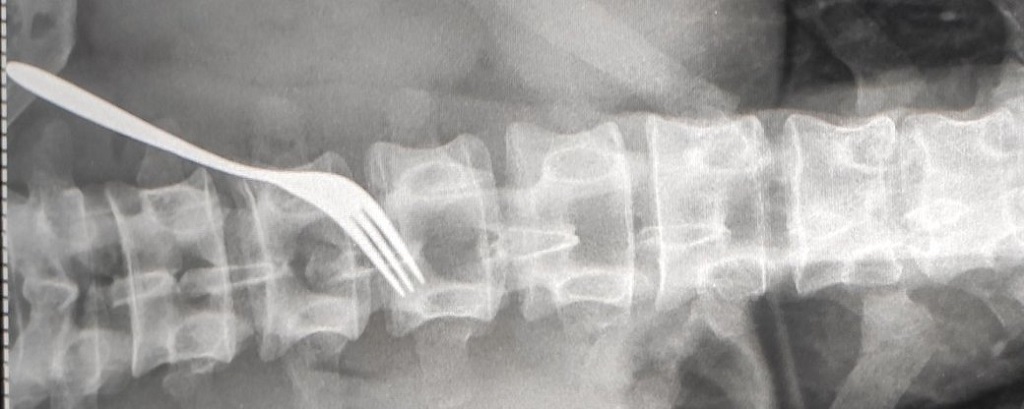

Виделку витягнули з чоловіка під час операції в Ужгородській міській клінічній лікарні. Хірургічне втручання провели 8 липня.

Про це сьогодні кореспондентам Суспільного розповів головний лікар Іван Курах. Зараз пацієнт перебуває в стані середньої важкості.

За словами медика, вилку пацієнт проковтнув 3-4 місяці тому: “Сталося це не гострим, а тупим кінцем. Це представник ромського населення. За 3-4 останні дні воно дуже спазмувало, подразнило слизову шлунку, тому вчора в нього були дуже різкі болі. Колеги були змушені брати його й оперувати. Забрали виделку і зашили стінку шлунку. У чоловіка порушена психіка”.